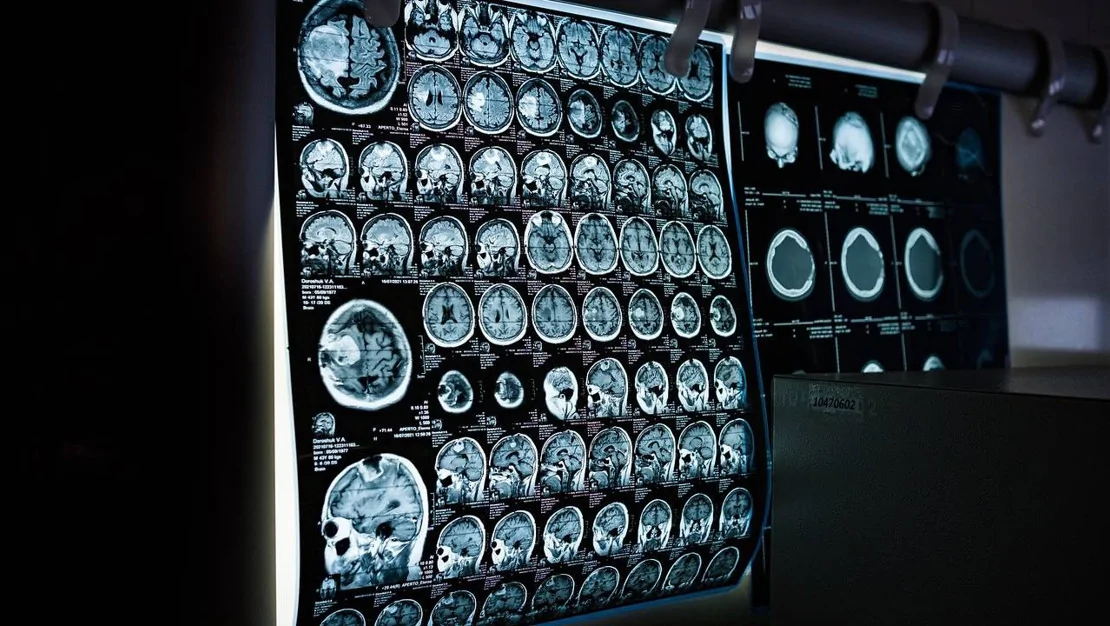

KANSER HASTALIKLARI VE ERKEN TANI

Bakanlık tarafından yapılan açıklamaya göre; kanser, hem Türkiye’de hem de dünyada en büyük halk sağlığı sorunlarından biri olarak öne çıkıyor. Erken teşhis konulan kanser türlerinde tedavi başarısı artıyor, bu da hastaların yaşam süresini ve yaşam kalitesini iyileştiriyor. Bu nedenlerden dolayı, daha fazla vatandaşın ücretsiz kanser tarama hizmetlerine erişim sağlaması ve tarama faaliyetlerine katılımının artırılması amacıyla kısa mesaj (SMS) ile bilgilendirme uygulaması hayata geçiyor.

ÜCRETSİZ KANSER TARAMA HİZMETLERİ

Ulusal Kanser Tarama Programı dahilinde, 40 ile 69 yaş aralığındaki kadınlara her iki yılda bir mamografi taraması ile meme kanseri, 30 ile 65 yaş arasındaki kadınlara beş yılda bir HPV-DNA testi ile serviks (rahim ağzı) kanseri ve 50 ile 70 yaş aralığındaki kadın ve erkeklere iki yılda bir gaitada gizli kan testi ile kolorektal (kalın bağırsak) kanseri taraması yapılıyor. Bu tarama işlemleri, Aile Sağlığı Merkezleri (ASM), Kanser Erken Teşhis, Tarama ve Eğitim Merkezleri (KETEM), Sağlıklı Hayat Merkezleri (SHM) ve mobil kanser tarama araçlarında tamamen ücretsiz olarak gerçekleştiriliyor.

KISACA 15 MİLYON KİŞİYE ULAŞILACAK

Sağlık Bakanlığı, bu yeni uygulama çerçevesinde meme kanseri taraması için yaklaşık 5,5 milyon, serviks (rahim ağzı) kanseri taraması için yaklaşık 3 milyon ve kolorektal (kalın bağırsak) kanseri taraması için de yaklaşık 6,5 milyon kişiye kısa mesaj göndermeyi planlıyor. Bu mesajlar, bir ay boyunca kademeli olarak gönderilecek ve hangi kanser türleri için tarama yapılabileceği, başvuru yöntemleri ve en yakın sağlık kuruluşlarının bilgileri hakkında bilgi verecek. SMS ile iletişime geçilecek yaklaşık 15 milyon kişi, kanser taramaları için belirlenen yaş aralığında olan bireylerden oluşuyor. İçlerinde daha önce kanser taramalarına katılmış olanlar da yer alıyor.